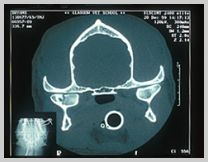

CT scan of fractured right mandibular

condyle

X-ray & CT images

courtesy of Glasgow University